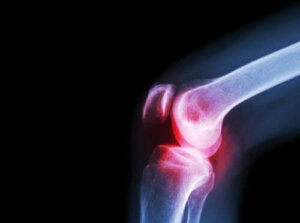

Należy zauważyć, że większość przypadków septycznego zapalenia stawów jest wywoływana przez bakterie, zwłaszcza gronkowce i paciorkowce. Może ono wprawdzie wystąpić w każdym wieku, najczęściej jednak występuje u niemowląt. Co więcej, dotyka głównie stawów biodrowych lub kolanowych.

Objawy powodowane przez septyczne zapalenie stawów różnią się w zależności od rodzaju zakażenia. Infekcje bakteryjne zwykle dotyczą tylko jednego stawu – kolana lub biodra. W takich przypadkach każdy ruch dotkniętego stawu jest bardzo bolesny. Ten ból, a także inne objawy, w tym gorączka i dreszcze, rozwijają się zwykle bardzo szybko.

Lekarz może również zlecić prześwietlenie chorego stawu. Zdjęcia rentgenowskie i inne sposoby diagnostyki mogą pomóc w ocenie stanu pacjenta.